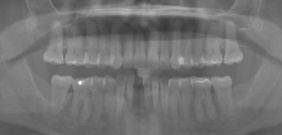

CLINICAL VIDEO NARRATED Immediate Tooth Replacement with Simultaneous Socket and

CAT# CV-095-L

NARRATED Immediate Tooth Replacement with Simultaneous Socket and Soft Tissue Graft with Narration

Dr. Sascha A. Jovanovic

CLINICAL VIDEO Immediate Tooth Replacement with Simultaneous Socket and Soft Tis

CAT# CV-095

Immediate Tooth Replacement with Simultaneous Socket and Soft Tissue Graft